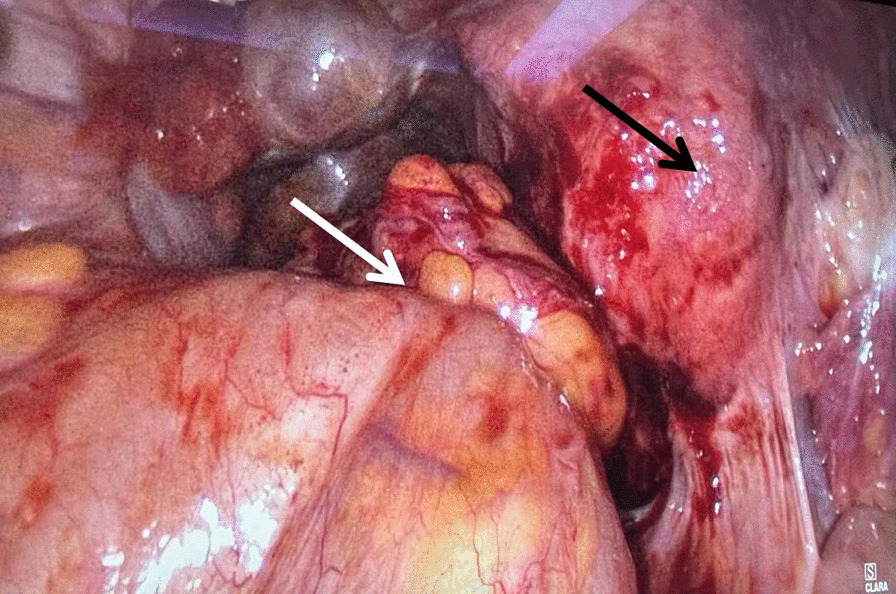

A primary diagnosis of intestinal obstruction secondary to rectal endometriosis was made according to the laboratory and instrument examinations. After 7 days of colon decompression and nutrition support therapy, the patient's abdominal distension was significantly relieved, CT reexamination showed that the dilatation of the colon was significantly less than before (Fig. 1D). An operation of laparoscopic partial rectal and sigmoid colon resection and total hysterectomy was performed successfully. The specimen was removed through a small abdominal incision (about 5 cm). During the operation, we found a stenosis recto-sigmoid mass and multiple adenomyoma of the uterus. The mass had adhesion with the posterior lamina of right broad ligament and the posterior uterine wall, without infiltration into the rectovaginal septum (Fig. 2).

Fig. 2.

During the operation, a stenosis recto-sigmoid mass (white arrow) and multiple adenomyoma of the uterus (black arrow) (H&E × 100)